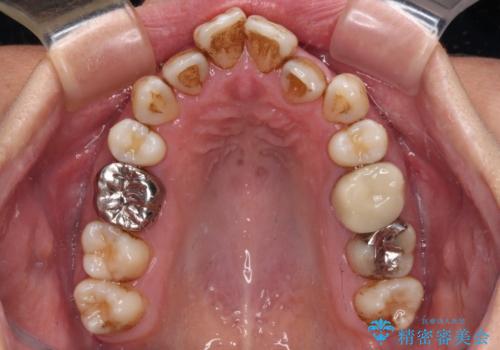

- かつて抜歯矯正を行ったものの、後戻りをしてしまったとのことで来院された患者様です。

上顎前歯が前突し、隣の歯が裏側に移動してきている状態でした。

飲み込みの状態を確認したところ、舌の突出癖が認められたため、それによる後戻りの可能性が高いと考え、舌のトレーニングを指導しました。

日頃から飲まれる飲み物の影響で着色しやすいため、来院の度に着色除去のクリーニングも行っていました。